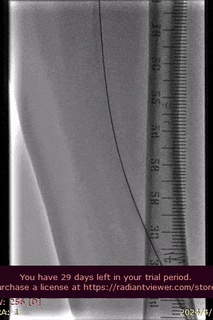

手术过程